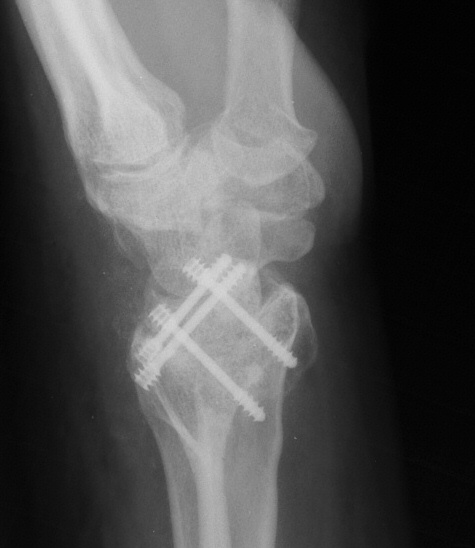

Clinical Example: Radioscapholunate Fusion and Triquetrum excision for Radiocarpal Arthritis

Radioscapholunate fusion is a treatment option for radiocarpal arthritis following distal radius fracture or associated with rheumatoid arthritis. Range of motion is usually less than half of normal following this procedure. Technical modifications to improve range of motion include distal scaphoid excision, or as in this case, triquetrum excision and excision of distal ulnar articular surface to manage ulnolunate abutment. There are a variety of fixation techniques. In this case, crossed Herbert screws were used: dorsal carpal bone to palmar radius and dorsal radius to palmar carpal bone.

Three months postop :